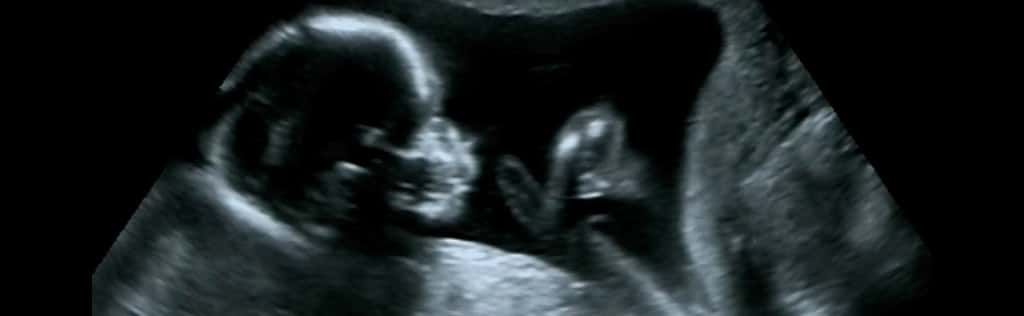

- Valutazione della crescita fetale (biometria)

- Valutazione della quantità di liquido amniotico e condizioni della placenta

- Flussimetria per la valutazione della circolazione materno-fetale